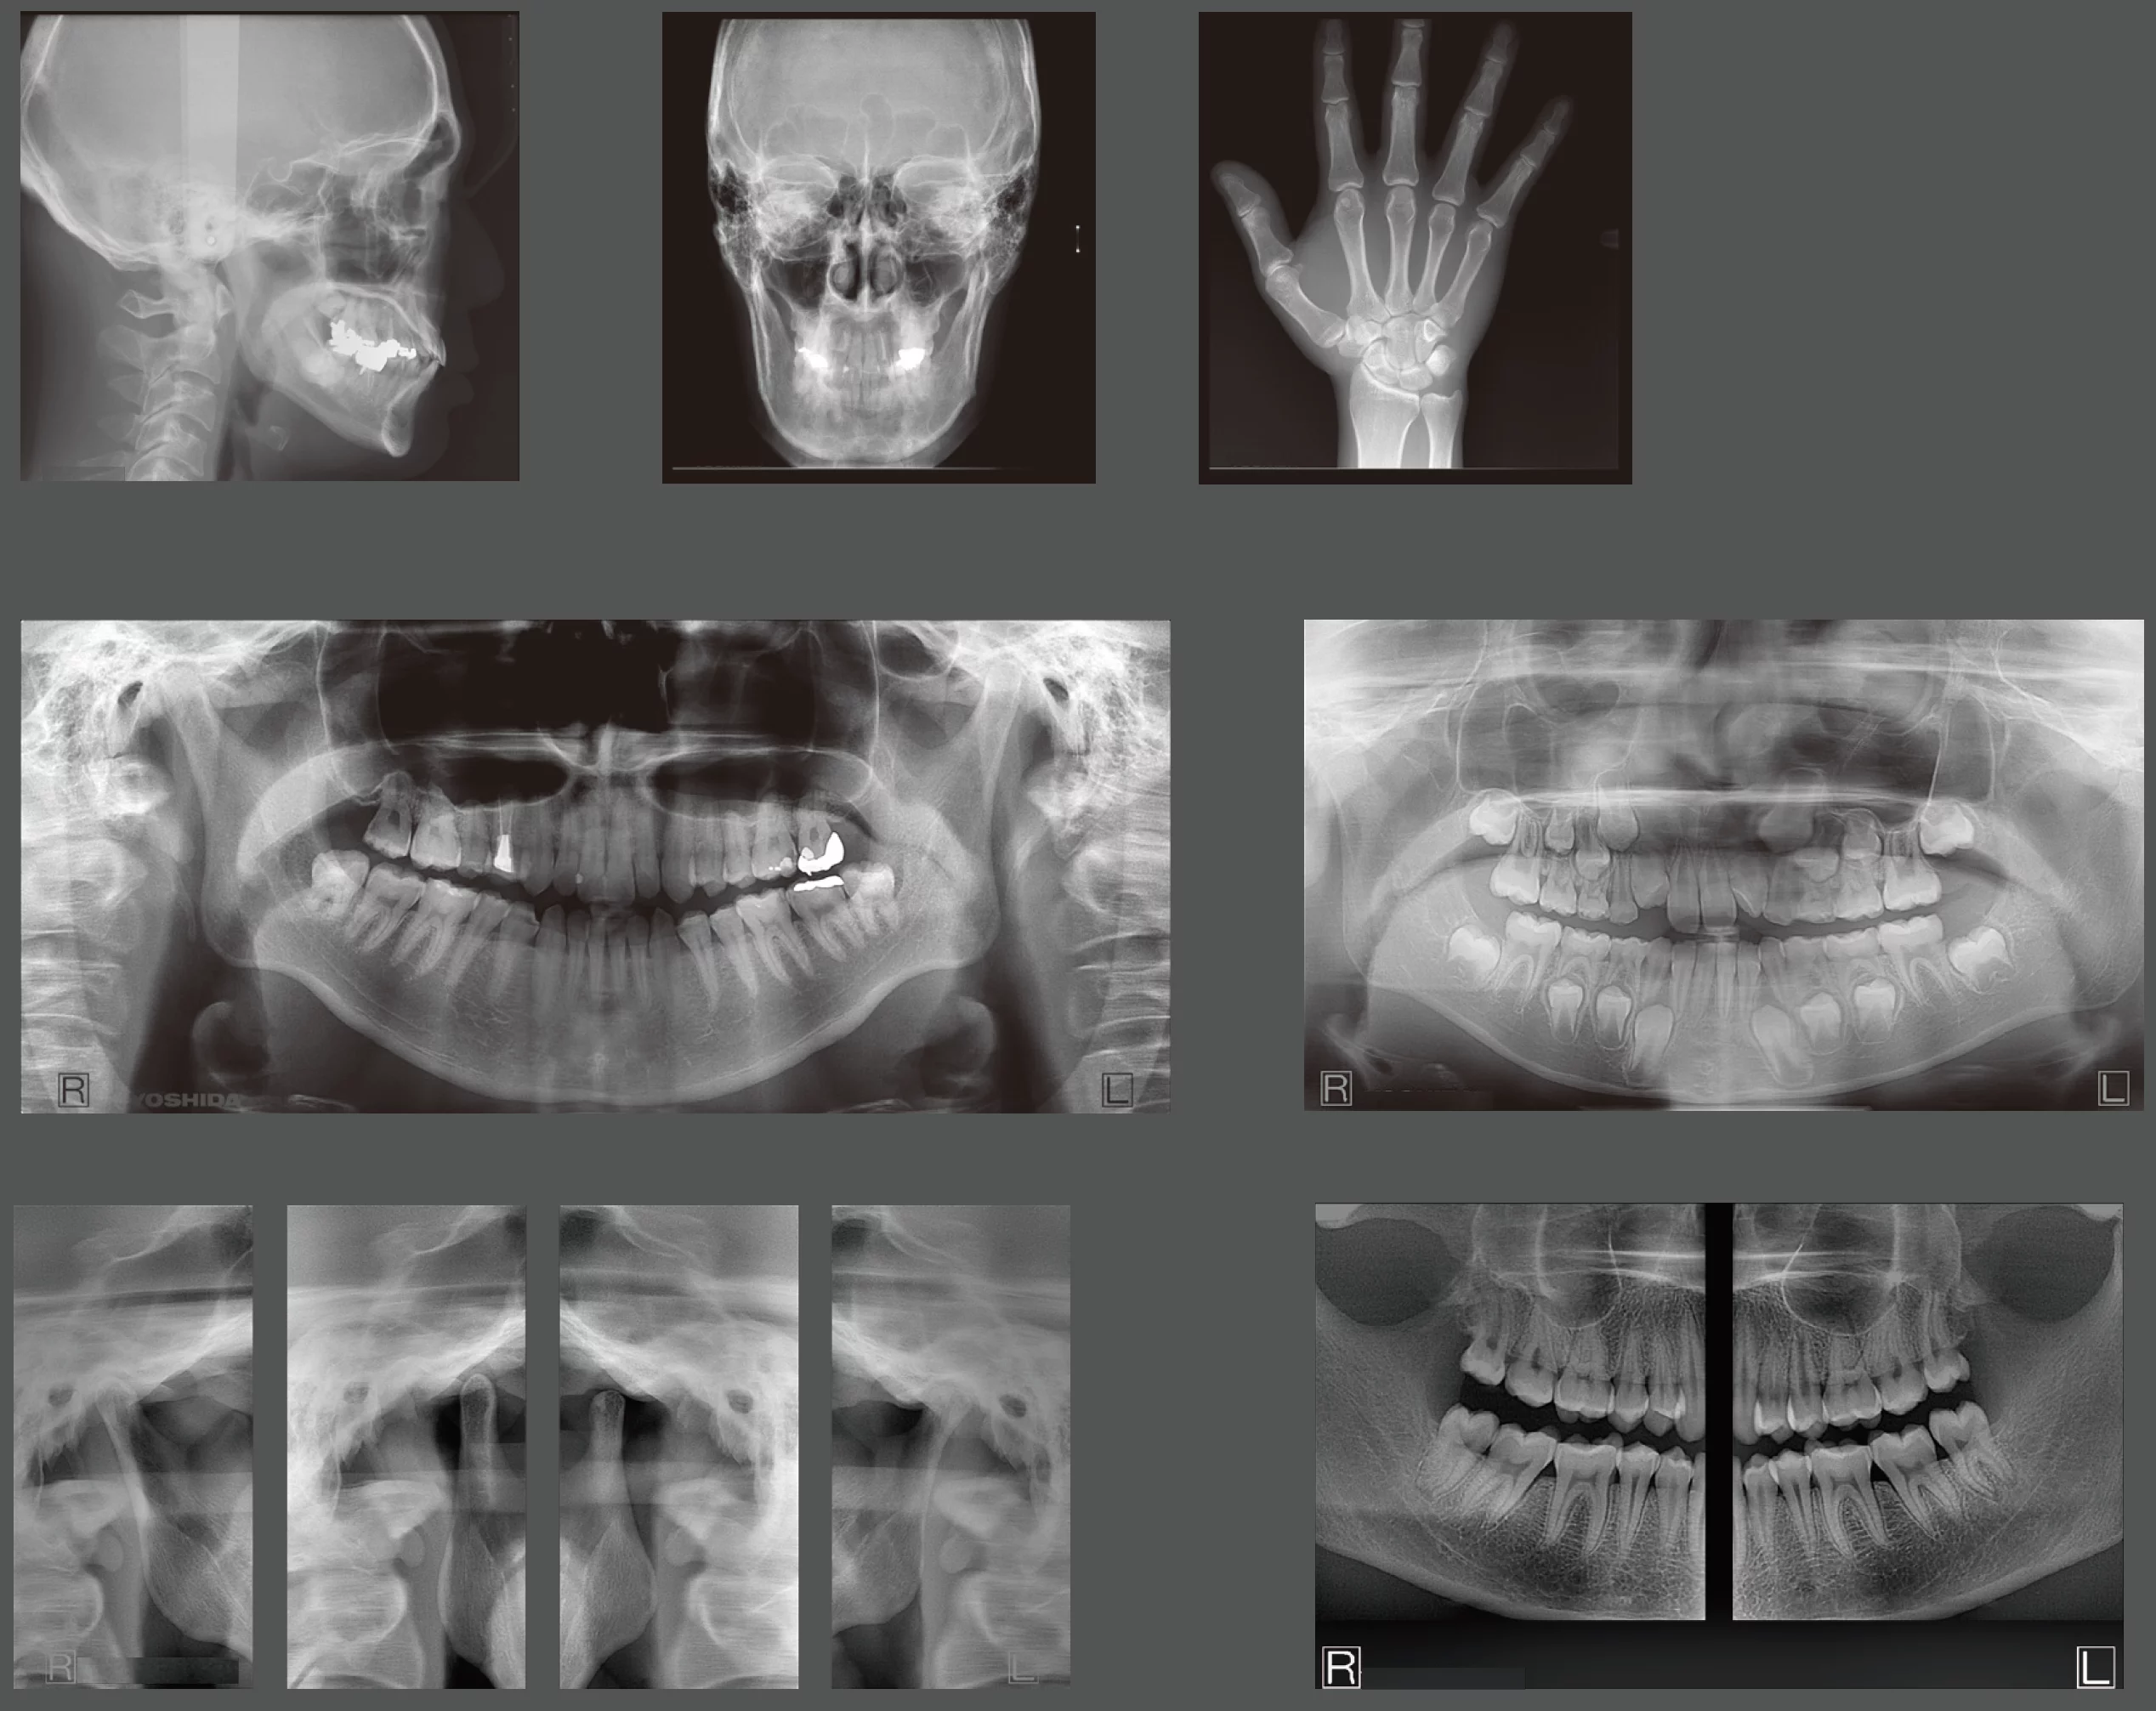

A Panoramic X-Ray to be proud of

Most of our dental professionals depend on their cone beam system to produce a high-quality panoramic x-ray in addition to a high-quality 3D volume. Most dental cone beam systems sacrifice the performance of their panoramic modality by attempting to use the 3D sensor to perform 2D panos. The X-era uses a cone beam sensor for cone beam scans, and a panoramic sensor for panoramic scans.

In fact, the panoramic sensor is the same high-quality sensor that we use in our wildly successful pan-only platform, the Panoura 18S. Here’s what makes the panoramic modality so powerful…

Every scan captures over 50 different panoramic layers!

The X-era also has Multi-Focal Plane capture capability. This means that every scan captures many layers both forward and backward. This creates a wide “envelope” where much more data is captured around where the patient is positioned.

Not only Bitewings, but an entire FMX!

Vertical bitewing feature as well as FMX Clipping feature creates 18 intraoral-sized images clipped from the pan with one click.

Ideal tool for patients who won’t tolerate traditional PAs

- Instead of taking 18 individual images with an intraoral X-Ray, they can all be generated at once in 14 seconds.

Review Sample Images and Volumes